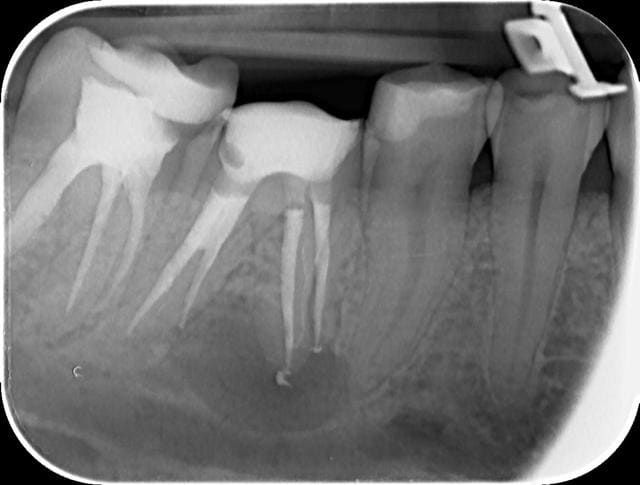

46 - fig 1,2 situation initiale

Fase du traitement: seule visite 2h

- percussion - positive

- teste du vitalité - négative

NaOCl 5% - l'irrigation et l'activation par ultrasons

chaud condensation de gutta-percha

Apres obturation - fig.3,4